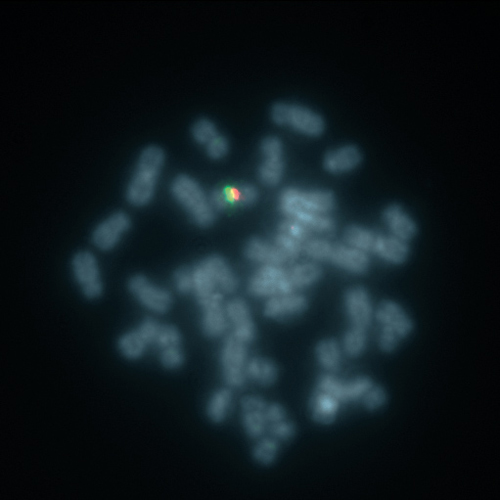

SE X (DXZ1) Red

KBI-20001R

SE 1 (1qh) Red

KBI-20028G

SE 14/22 Green